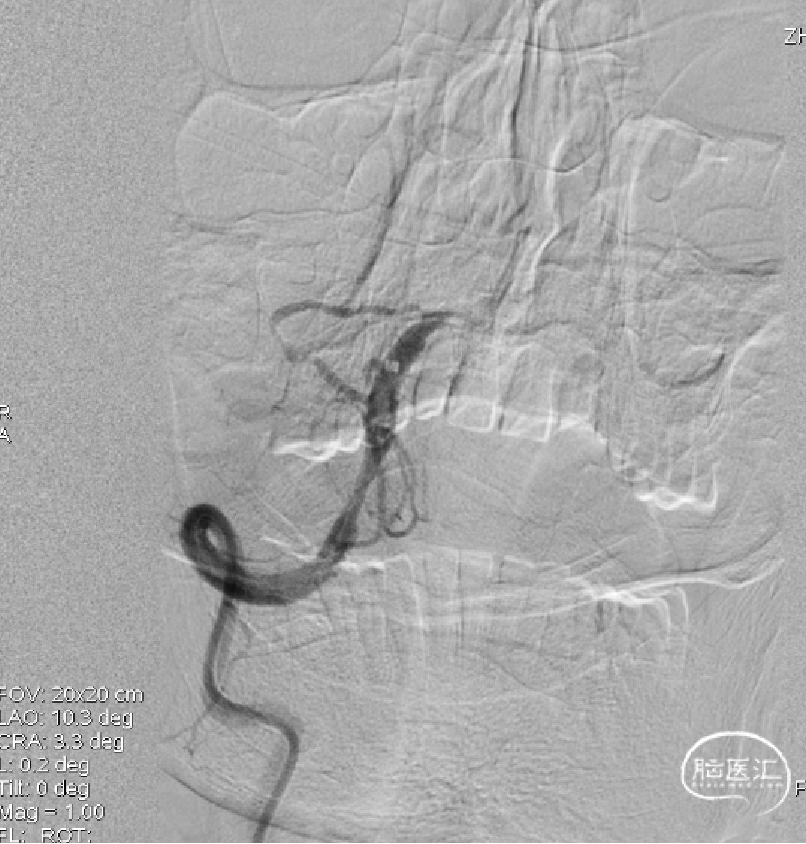

1、考虑右侧椎动脉V4段闭塞,不再犹豫,即刻选择左侧椎动脉入路;2、左侧椎动脉造影:提示V4段末端瘤样扩张伴基底动脉近端重度狭窄。

ACE60抽吸导管+RECO 4×20mm取栓支架抽拉结合,造影示基底动脉近端重度狭窄,远端通畅。

1、取栓两次,第二次将尼科支架置于狭窄处;2、第二次取栓后造影基底动脉近端重度狭窄,远端通畅。